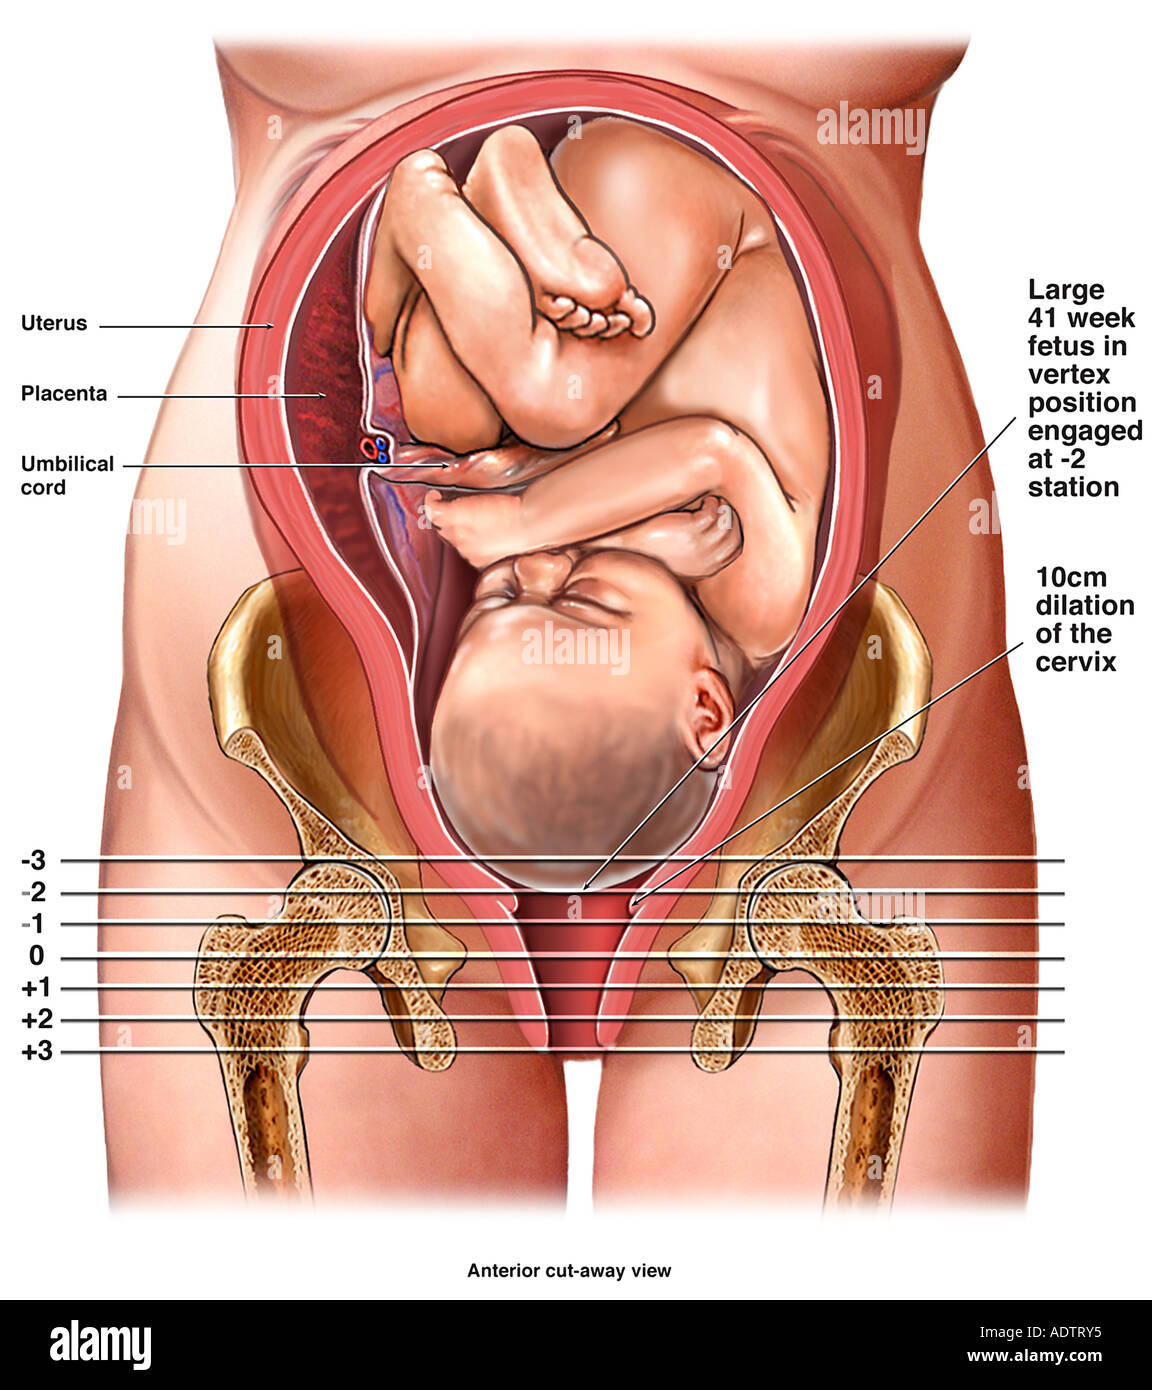

Головка ребенка опустилась в таз

Longitudinal Lie and Cephalic position of child